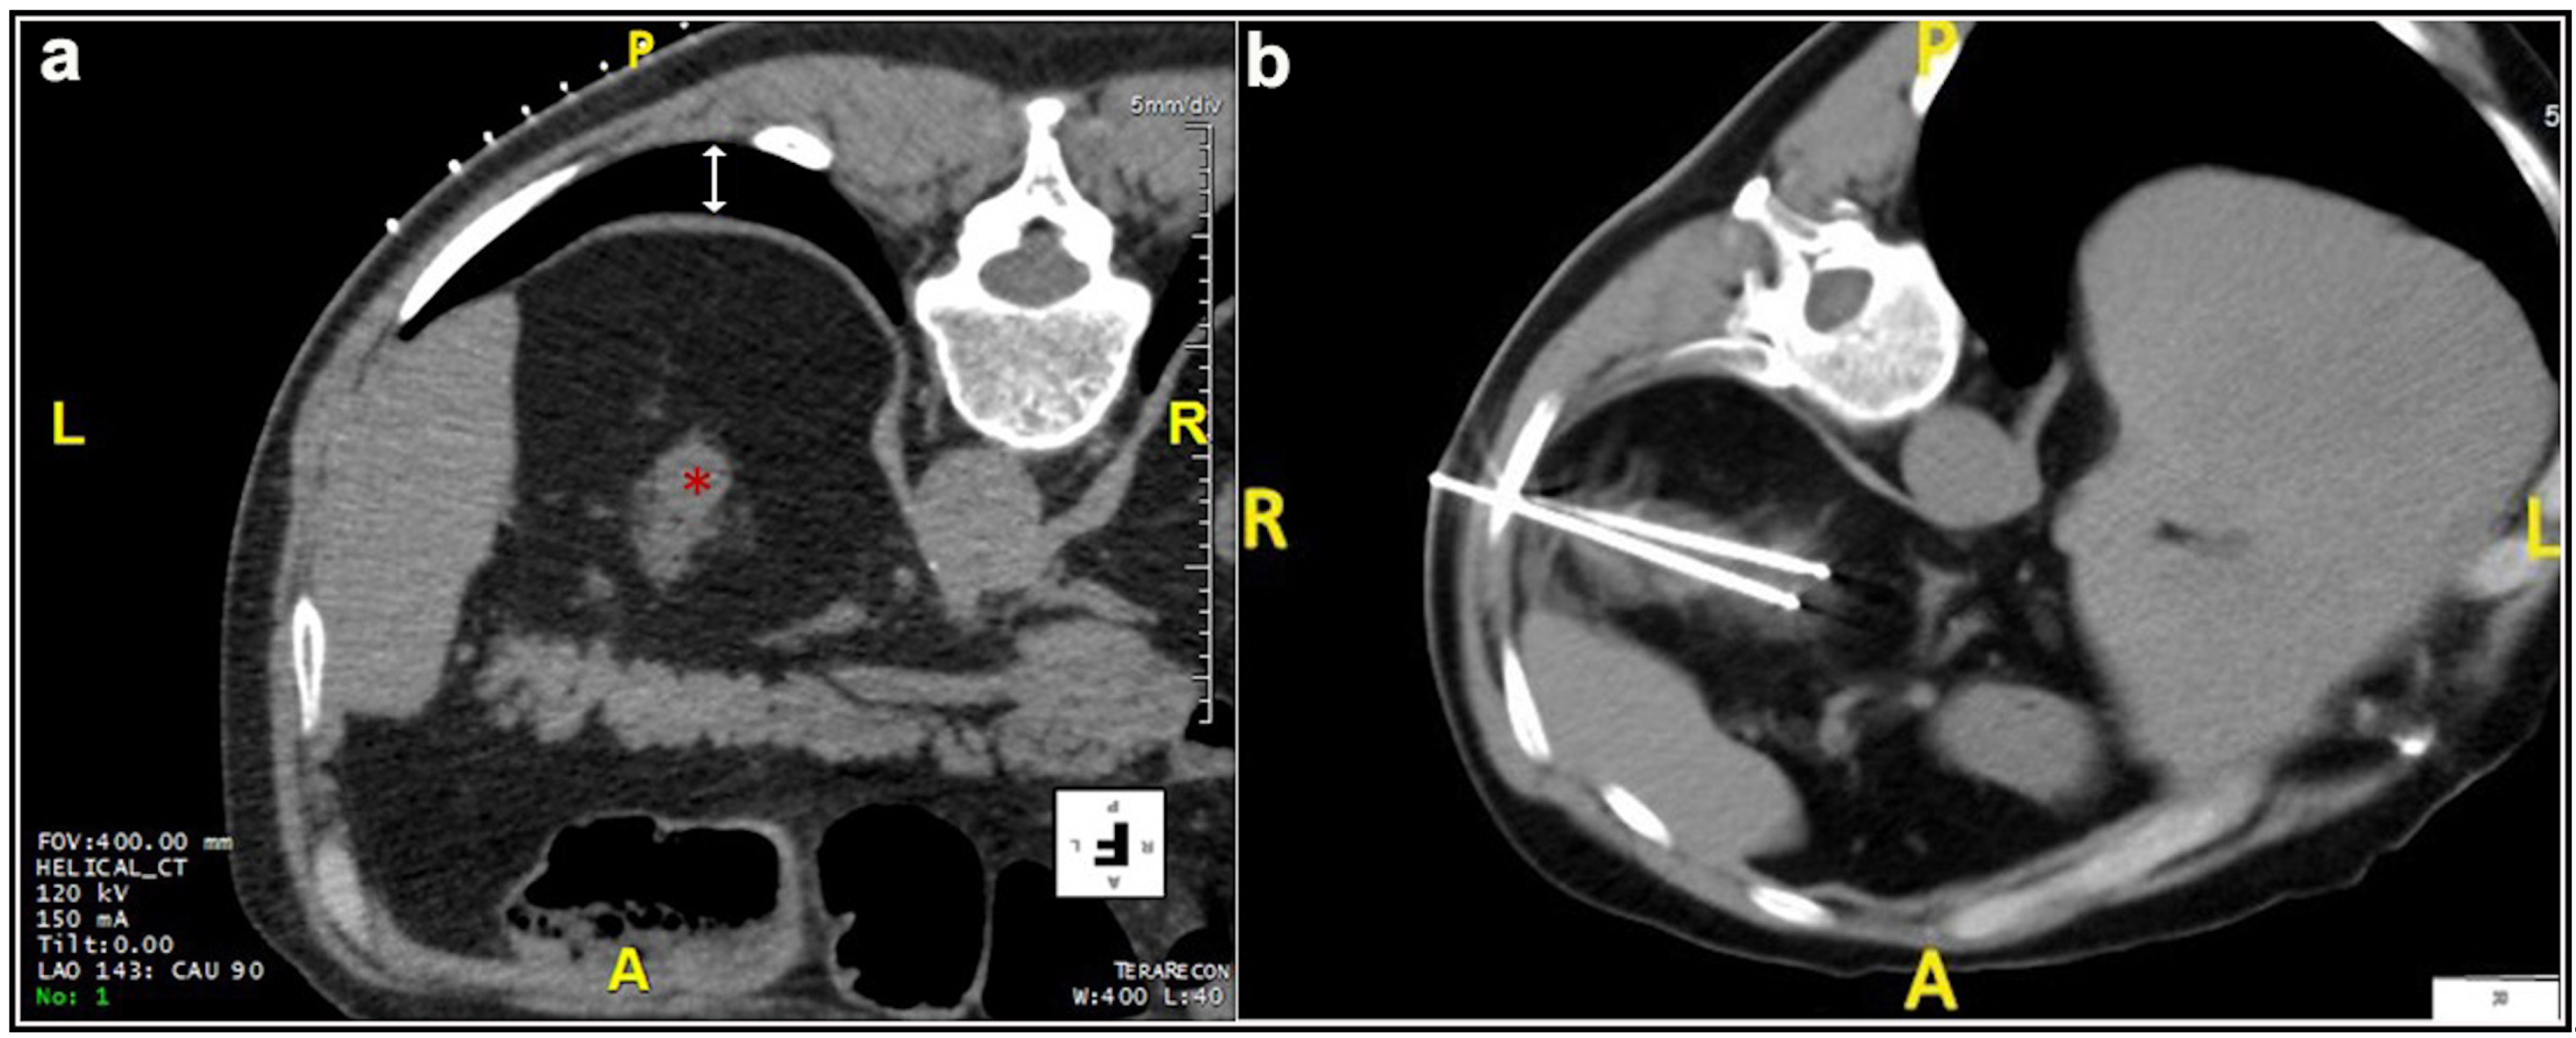

Most patients (87.4%) were treated prone. Twenty patients were treated in the oblique or lateral decubitus position (Figure 1). Only two treatments were carried out with the patient supine. Local anesthesia was mostly sufficient for the large majority of the procedures and mild conscious sedation was administered if needed. One patient required general anesthesia for the impossibility to collaborate with breath holds during the procedure because of dementia. In most cases, one lesion was treated in each procedure. In five patients, two lesions were treated in the same procedure, and, in another two patients, three lesions and four lesions were treated in a unique procedure, respectively. A median of two cryoprobes were used for each intervention (range: 1–8). Eight cryoprobes were required for the treatment of one of the largest tumors (5.4 cm), which revealed to be a clear-cell carcinoma at biopsy. The procedure was technically successful, and no complications occurred. Eighty-nine lesions required a complex cryoprobe approach. Hydro-dissection was necessary for the treatment of 13 tumors due to the vicinity of the bowel that could not be displaced after changing the position of the patient (Figure 2). In two cases, emptying of a cyst adjacent to the lesion was deemed necessary. Only one patient required a trans-hepatic approach (Figure 3). The procedures had a median duration time of 84 min (range: 40–153). Data on radiation exposure was available for 113 out of 138 patients with a median radiation exposure of 43.7 mSv.

Figure 3. Male, 78 years old. (a) The initial scan shows a lesion (*) located at the upper pole of the right kidney covered by the costophrenic sinus posteriorly (white arrow) and the hepatic parenchyma laterally. (b,c) The lesion was adequately treated with two cryoprobes inserted through the hepatic parenchyma in order to avoid pneumothorax. No complications occurred.